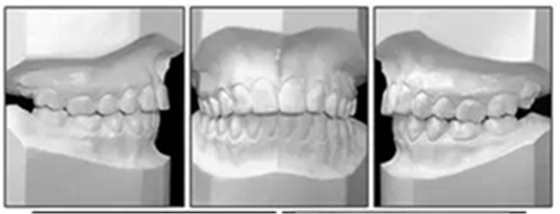

6年后治療結(jié)果保持穩(wěn)定(圖11,圖12 ; 圖13)??梢杂^察到穩(wěn)定的間隙關(guān)閉,正常的覆蓋和覆合,上下牙中線一致,微笑美觀。建議完美替代了拔除的側(cè)切牙。正畸治療后進(jìn)行牙齒美白。

頭顱測量疊加(圖14)顯示,面部特征在治療過程中發(fā)生變化,并在6年的隨訪評估中保持穩(wěn)定。上頜骨和下頜骨的區(qū)域疊加也表明治療期間的單純牙齒移動和骨骼穩(wěn)定性。在后續(xù)檢查中獲得并維持適當(dāng)?shù)母采w和覆蓋(表格)。